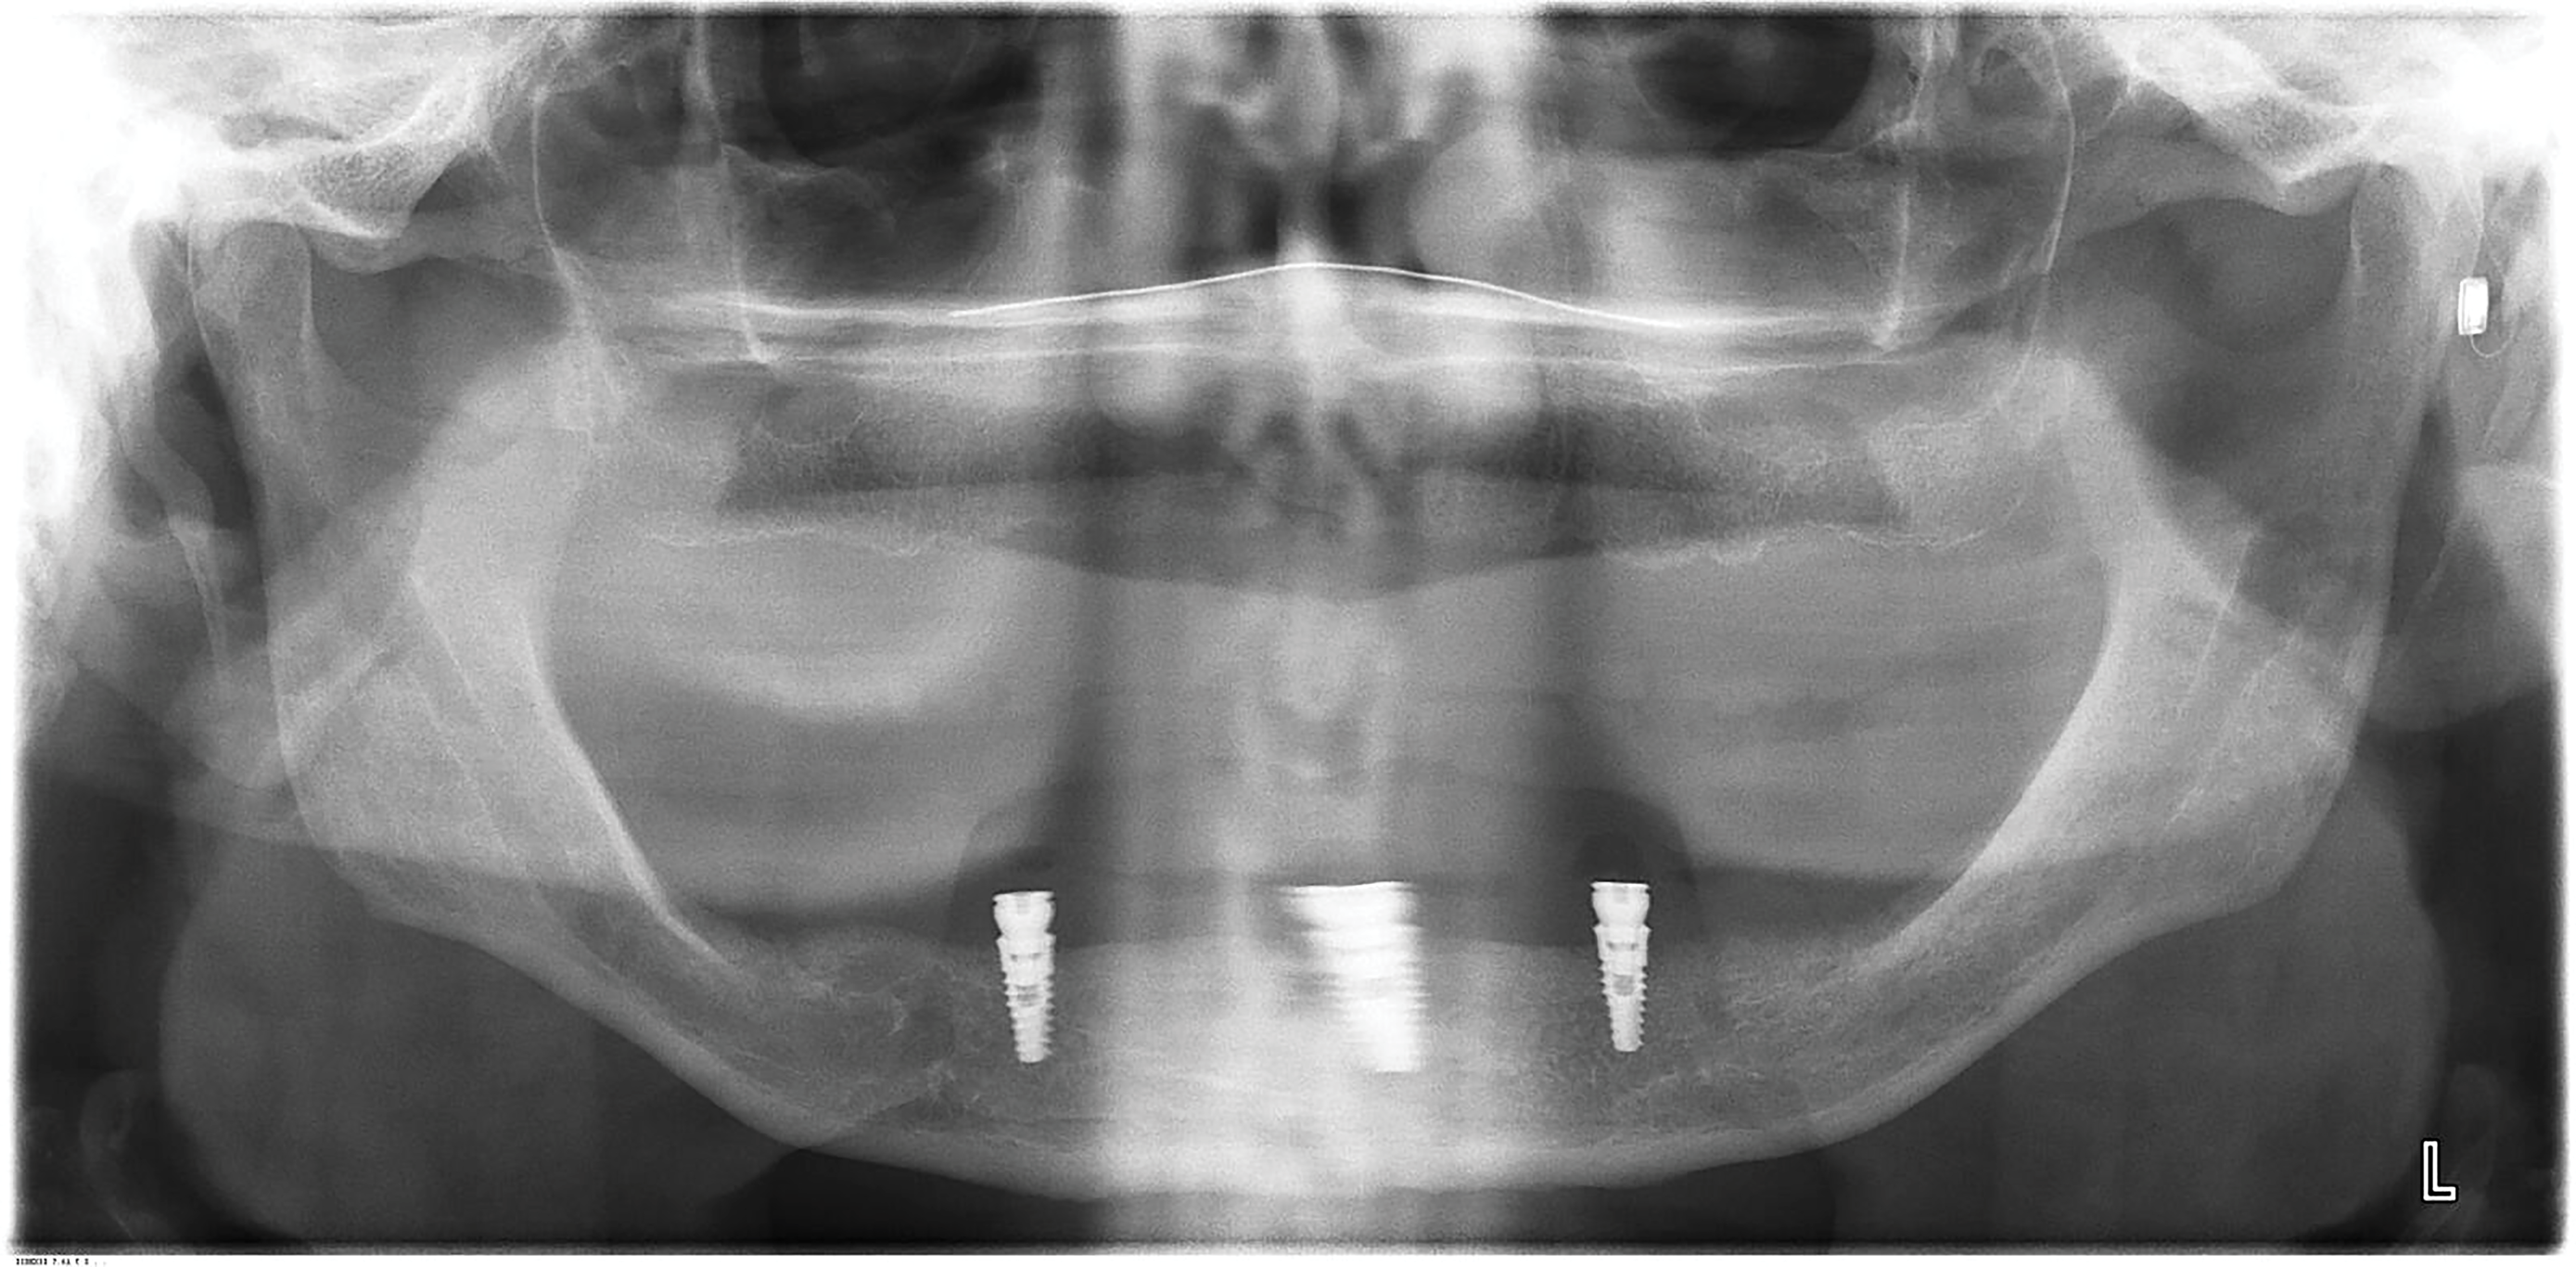

Implants were placed in sites Nos. 27 and 22 (3.8 mm x 9 mm) and site No. 24 (3.8 mm x 10.5 mm). At the 3-month follow-up appointment, all implants were well osseointegrated clinically and radiographically (Figure 6 and Figure 7) with no atypical or pathological findings, and the patient was referred to the denturist for prosthetic rehabilitation.

Six months after his last visit, the patient presented with complaints of unresolved pain in the lower gums and a referral from the denturist to assess the mandibular anterior region. The patient reported ongoing pain lasting more than 10 days without resolution despite repeated adjustments by the denturist to relieve areas of irritation. An area of ulceration was noted on the lingual gingiva of implant site No. 24, and a panoramic radiograph showed crestal peri-implant bone loss and thread exposure on all three implants (Figure 8), but this was unrelated to the observed lesion. Percussion of implant No. 24 and palpation of the buccal aspect did not yield a painful response. The tissue cuff surrounding the locator-type abutment was sensitive to palpation and localized to the lingual frenum adjacent to the implant.

Fig 7. Panoramic radiograph of implants following placement of locator-type attachments (3-month follow-up). Implants were well integrated with normal-appearing peri-implant bone.

Figure 7

Fig 8. Panoramic radiograph of implants at 6-month follow-up. Significant bone loss and thread exposure were noted around not only the affected implant No. 24 but all three implants.

Figure 8